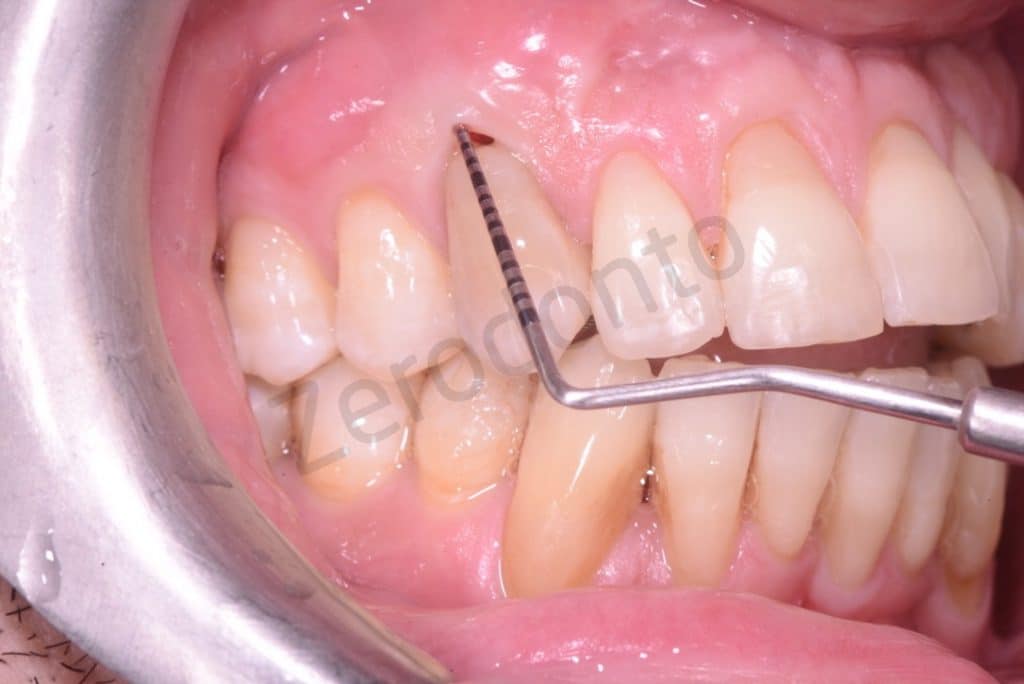

Initial situation

Probing resorption

4mm lesion